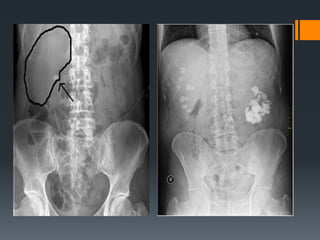

Kidney Stones : Renal calculi caused by

deposits of mineral salts in the kidney

Kidney Stones :Renal calculi caused by deposits of mineral salts in the kidney